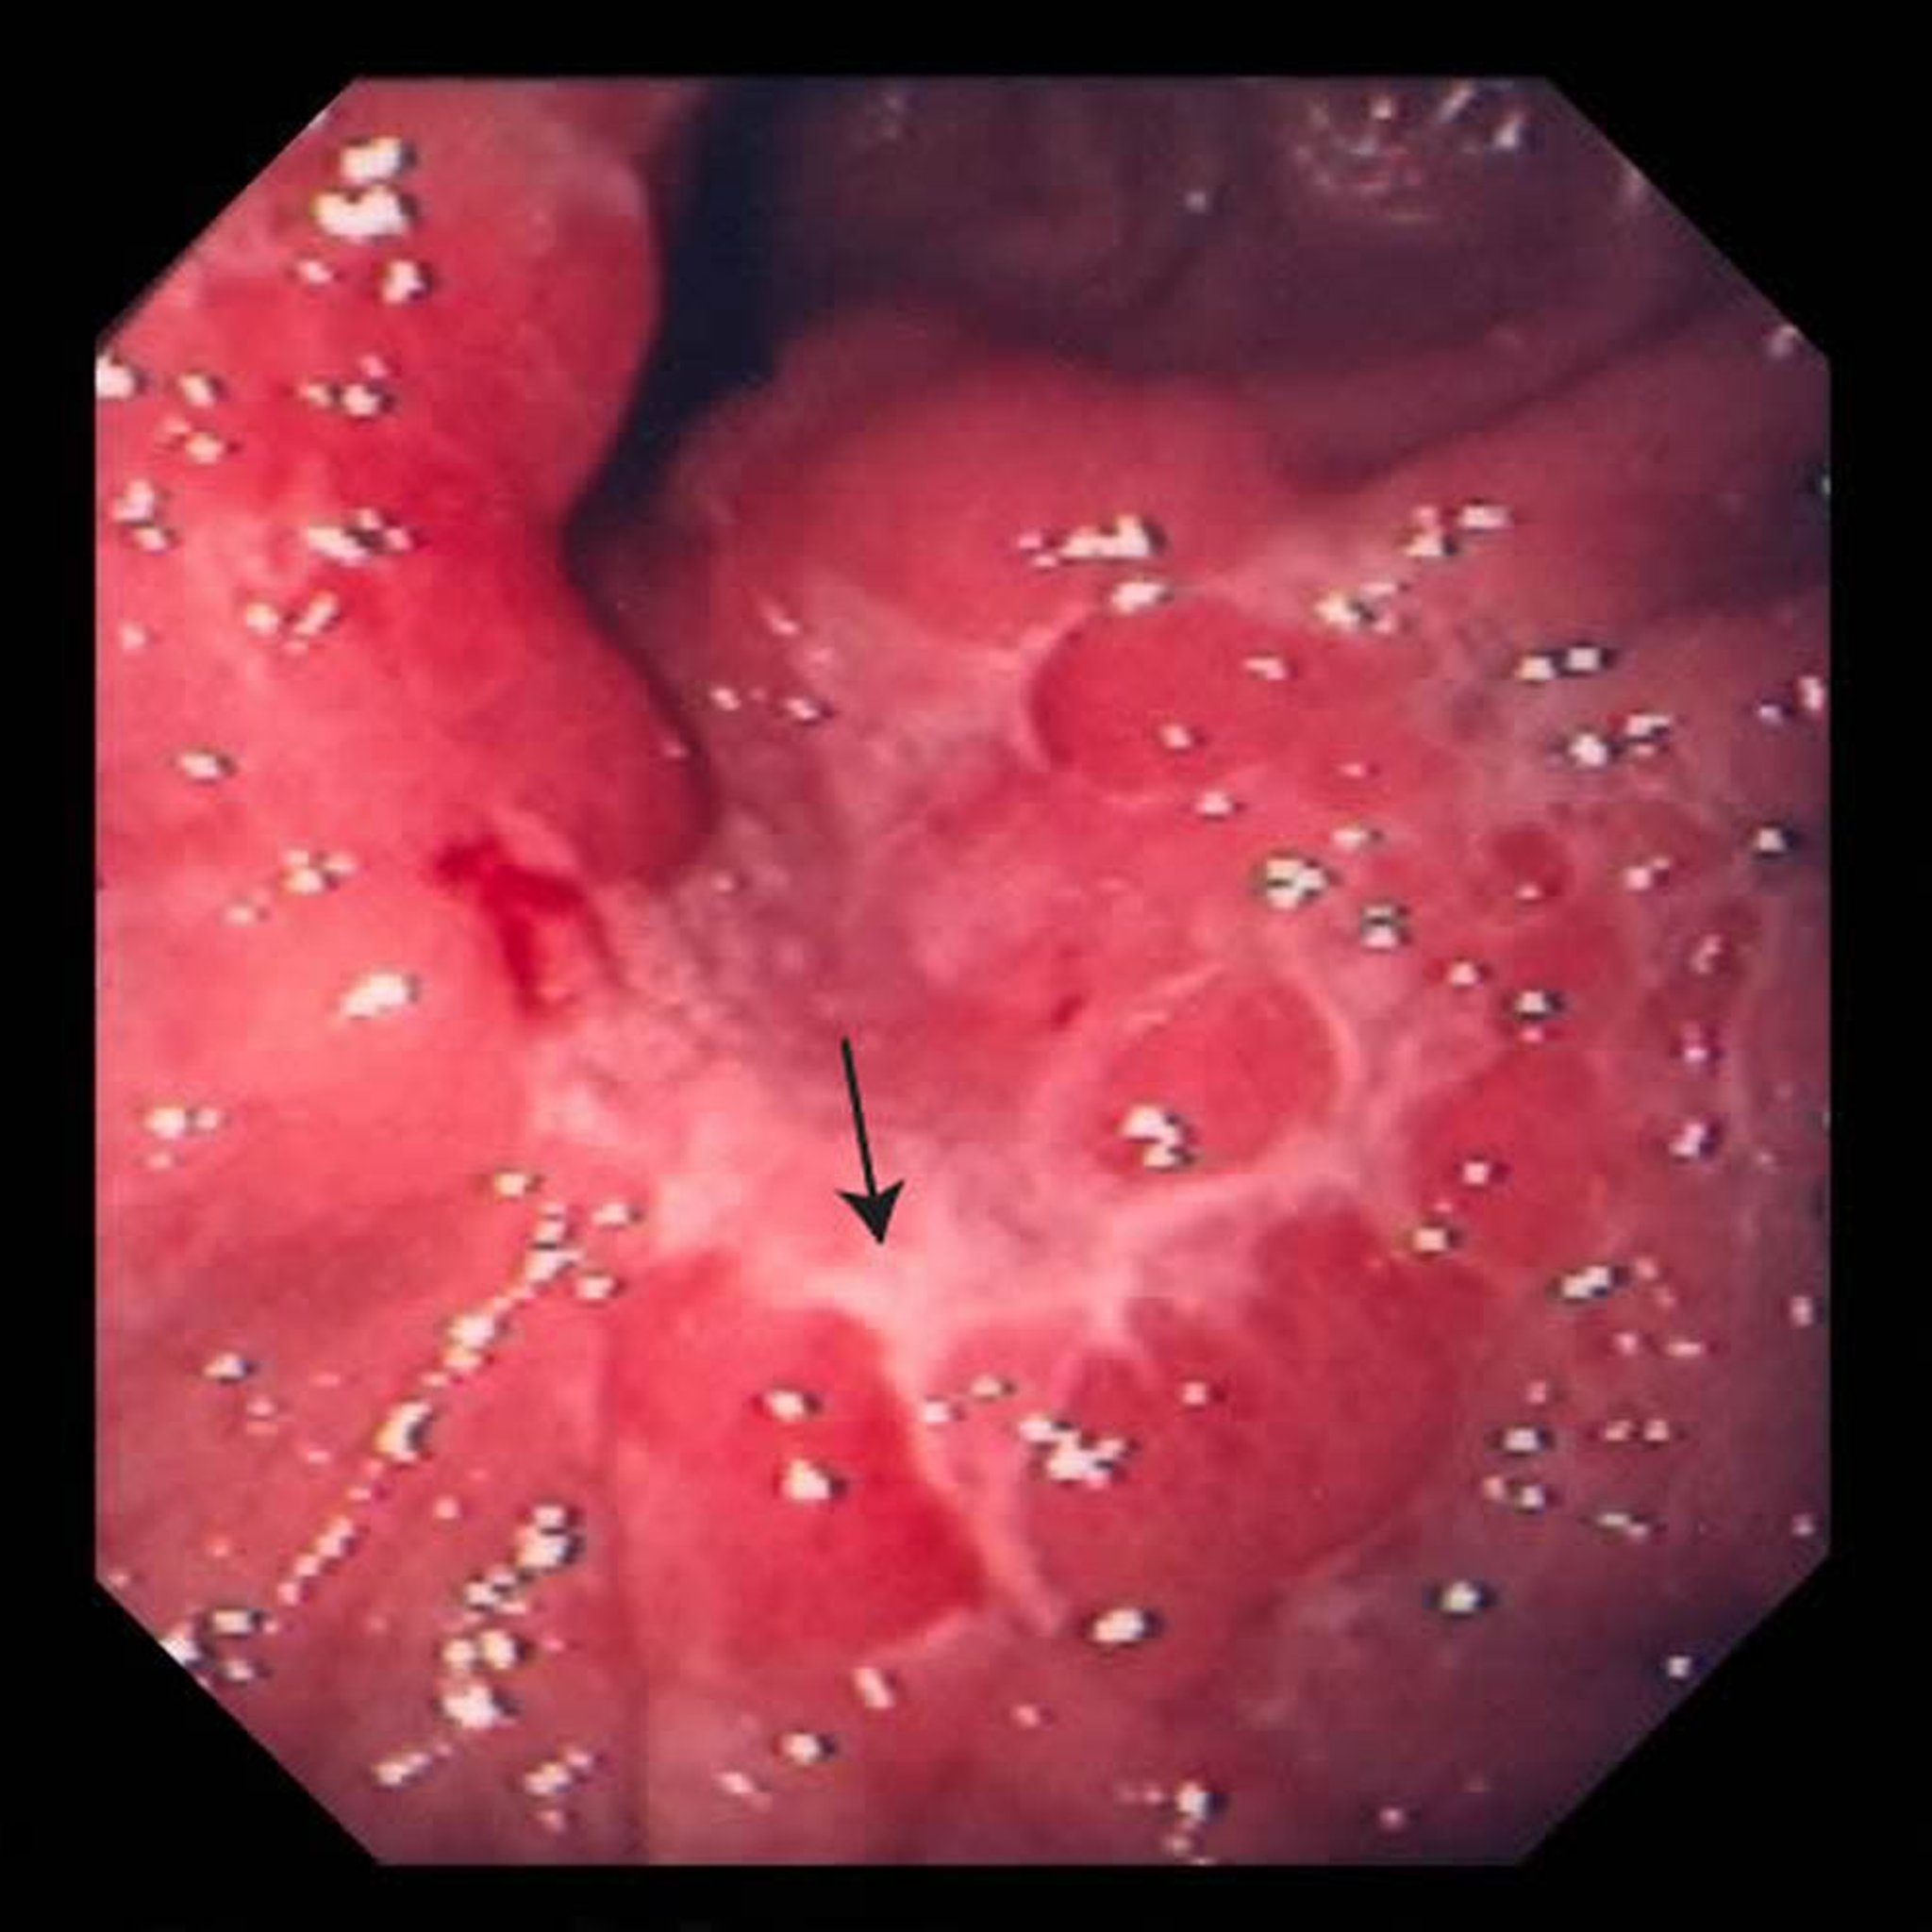

위암

이 사진은 위의 궤양(화살표)을 보여줍니다. 생검 후, 의사는 이를 샘암종이라 판단했습니다.

영상 제공: 의학박사 데이비드 M. 마틴(David M. Martin)